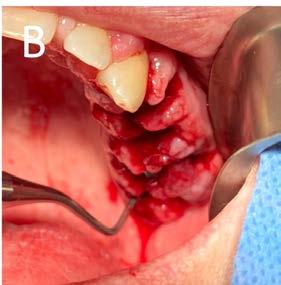

7. A) Extracción de órganos dentarios sin salvación. B) Legrado alveolar. C) Exéresis de tejido hiperplásico.

D) Sinéresis de los tejidos.

Posteriormente se abordó la fase quirúrgica: se realizaron las extracciones de los órganos dentarios sin posibilidad de mantenerse en función en boca, se efectuó el legrado alveolar para retirar tejido infectado, además de realizar la exéresis del tejido hiperplásico, y regularización ósea para posteriormente producir la sinéresis de los tejidos a través de una sutura continua simple con sutura absorbible Vicryl 3-0 (Figura 7).